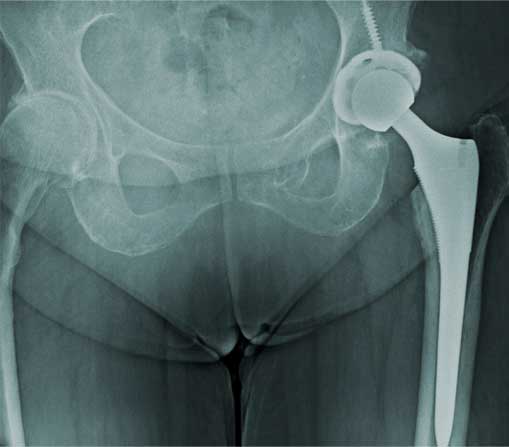

Fractura

de cadera

Es la pérdida de la continuidad del tejido óseo en la articulación de la cadera, producidas por caídas o traumatismos de alta energía, la cual se caracteriza por dolor intenso, incapacidad funcional, chasquidos, acortamiento y rotación de la pierna, el diagnóstico definitivo es por radiografía o tomografía.

¿Por qué se realiza?

El tratamiento en pacientes adultos regularmente es quirúrgico, el cual se realiza con implantes de metal que recuperan la anatomía normal de la articulación similar a la previa fractura, los cuales pueden ser clavos, placas, tornillos o prótesis.

Cuidados después de la intervención

La intención de un tratamiento de fractura siempre es movilizar al paciente lo más pronto posible, los tiempos para movilizar al paciente puede ser desde el primer día del tratamiento hasta algunas semanas dependiendo del tipo de fractura, tipo de paciente y el implante utilizado.

Resultados esperados

El objetivo es recuperar la función previo a la fractura con la misma fuerza, movimiento y estabilidad, esto se puede lograr si se realiza un diagnóstico adecuado y un tratamiento con una buena planeación.